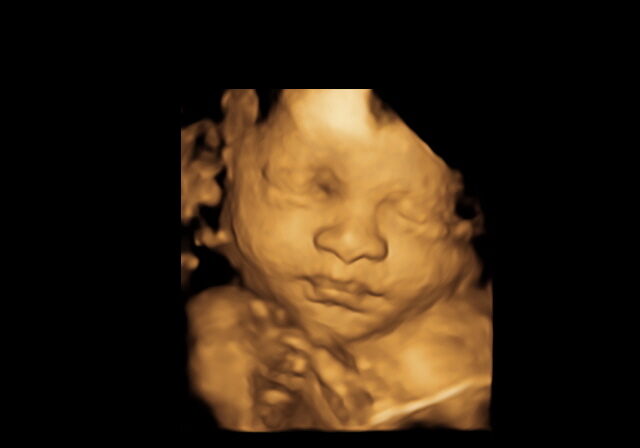

3D ultrasound image of a baby's face in the womb.

With state of the art GE technology we can bring your baby’s first smile and more to you, in high definition, to treasure for a lifetime. During a 3D/4D scan we may be able to capture your little one yawning, blinking, or even sticking out their tongue! This is a wonderful bonding experience for all.